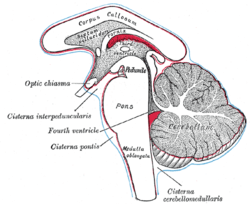

Diagram showing the positions of the three principal subarachnoid cisternae (pons visible at center) | |